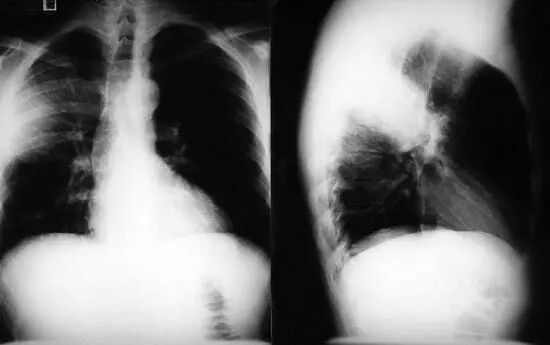

图1.9 49岁肺炎球菌性肺炎患者, 胸部X线片显示左下叶不透明伴胸腔积液。